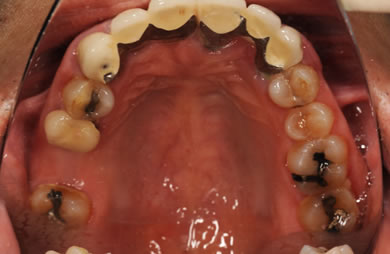

治療前

• 治療前